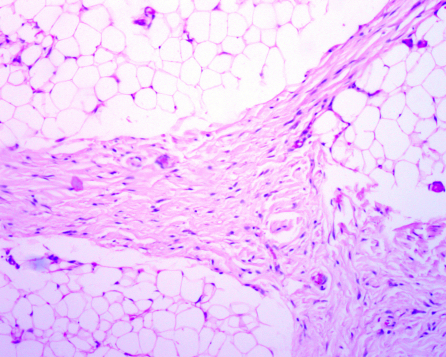

An 18-months-old male developed a tumor on his right upper eyelid over the course of two months. The tumor became significantly prominent, progressive enlargement over the last month. There was history of trauma to the area. On physical examination he was found to have a very large tumor, approximately 2×2 cm on the right upper eyelid, there appeared to be no discolorations, erythema, or signs of inflammation, it was a firm mass, and nontender to the palpation (Figure 1 [Fig. 1]). The remaining ocular examination was normal. The patient had no systemic manifestations. Orbital CT images demonstrated a large, well-circumscribed mass with a low density signal similar to intraorbital fat on the right upper eyelid. MRI presented a lesion with high signal intensity in T2-weighted images, and the lesion showed a well-marginated soft tissue mass with mixed signal intensity in T1-weighted images (Figure 2 [Fig. 2]). The superior visual field was compromised secondary to mechanical ptosis. The patient underwent an uncomplicated anterior orbitotomy through a superior eyelid crease incision and excision of the tumor (Figure 3 [Fig. 3]). The histological examination of the specimen revealed a lesion composed of mature adipose lobes separated by thick dense connective tissue tracts providing the diagnosis of a fibrolipoma (Figure 4 [Fig. 4]). At follow-up four years postoperatively the cosmetic appearance of the eyelid was very satisfactory and there had been no recurrence of the tumor.

Figure 4: Microscopy showed a lesion composed of mature adipose lobes separated by thick dense connective tissue tracts (H and E, x20).